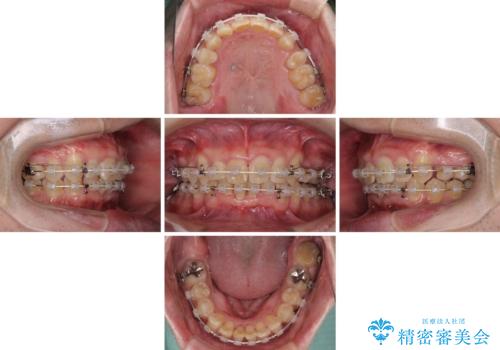

上顎歯列の叢生が著しかったため、上顎左右第一小臼歯2本を抜歯し、目立たないワイヤー装置にて治療を進めることとしました。